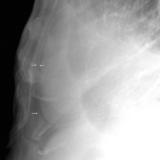

Peric stripe - slightly thickened

close up